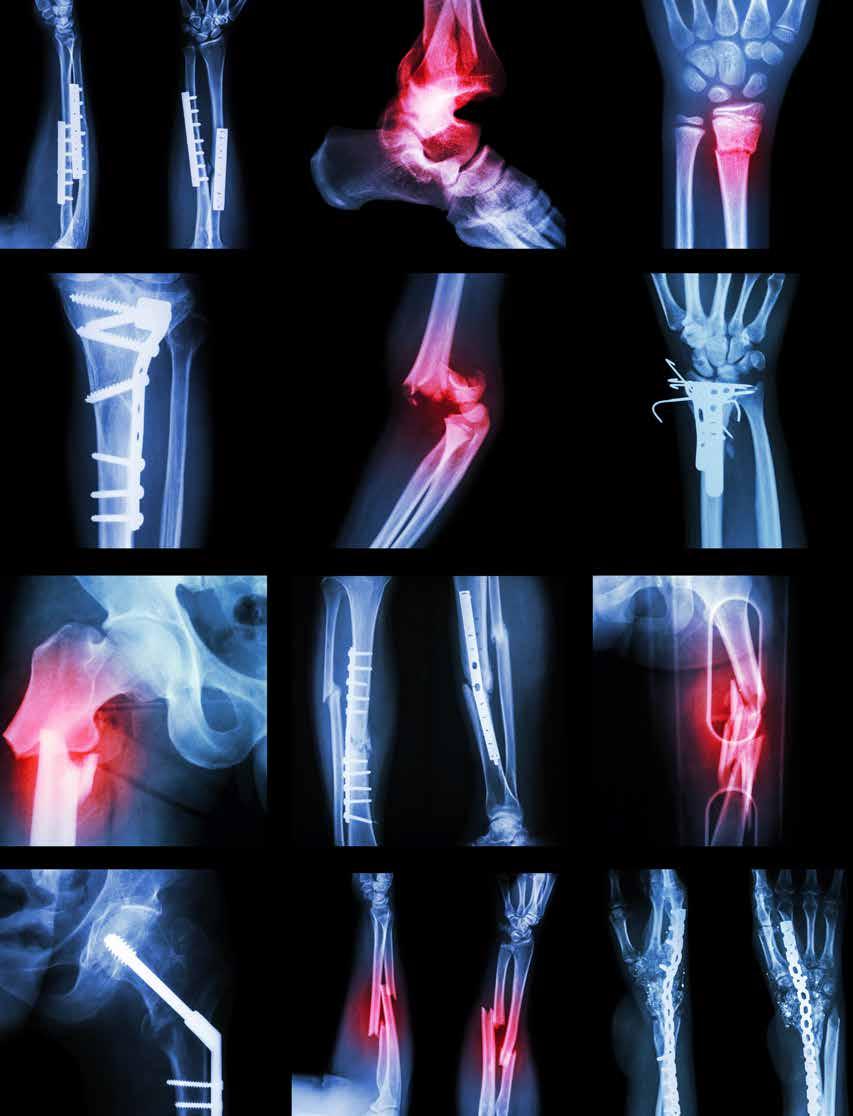

- Choose Hughston Clinic Orthopaedics -

OUR PHYSICIANS SPECIALIZE IN:

Upper Extremity | Lower Extremity | Joint Replacement | Sports Medicine General Orthopaedics | Spine | Trauma | Orthobiologics

ANN BEADLE, RN, ACNP

JOHN R. BURLESON, MD

JONATHAN P. CORNELIUS, MD

WILLIAM N. MELTON, MD

KRISTINA MOORE, PA-C

SHAWN P. MOUNTAIN, DO LUCAS B, RICHIE, MD

ASHELY N. SCOTT, PA-C

MICHEL A. TAYLOR, MD

(615) 547-6700 | tn.hughston.com